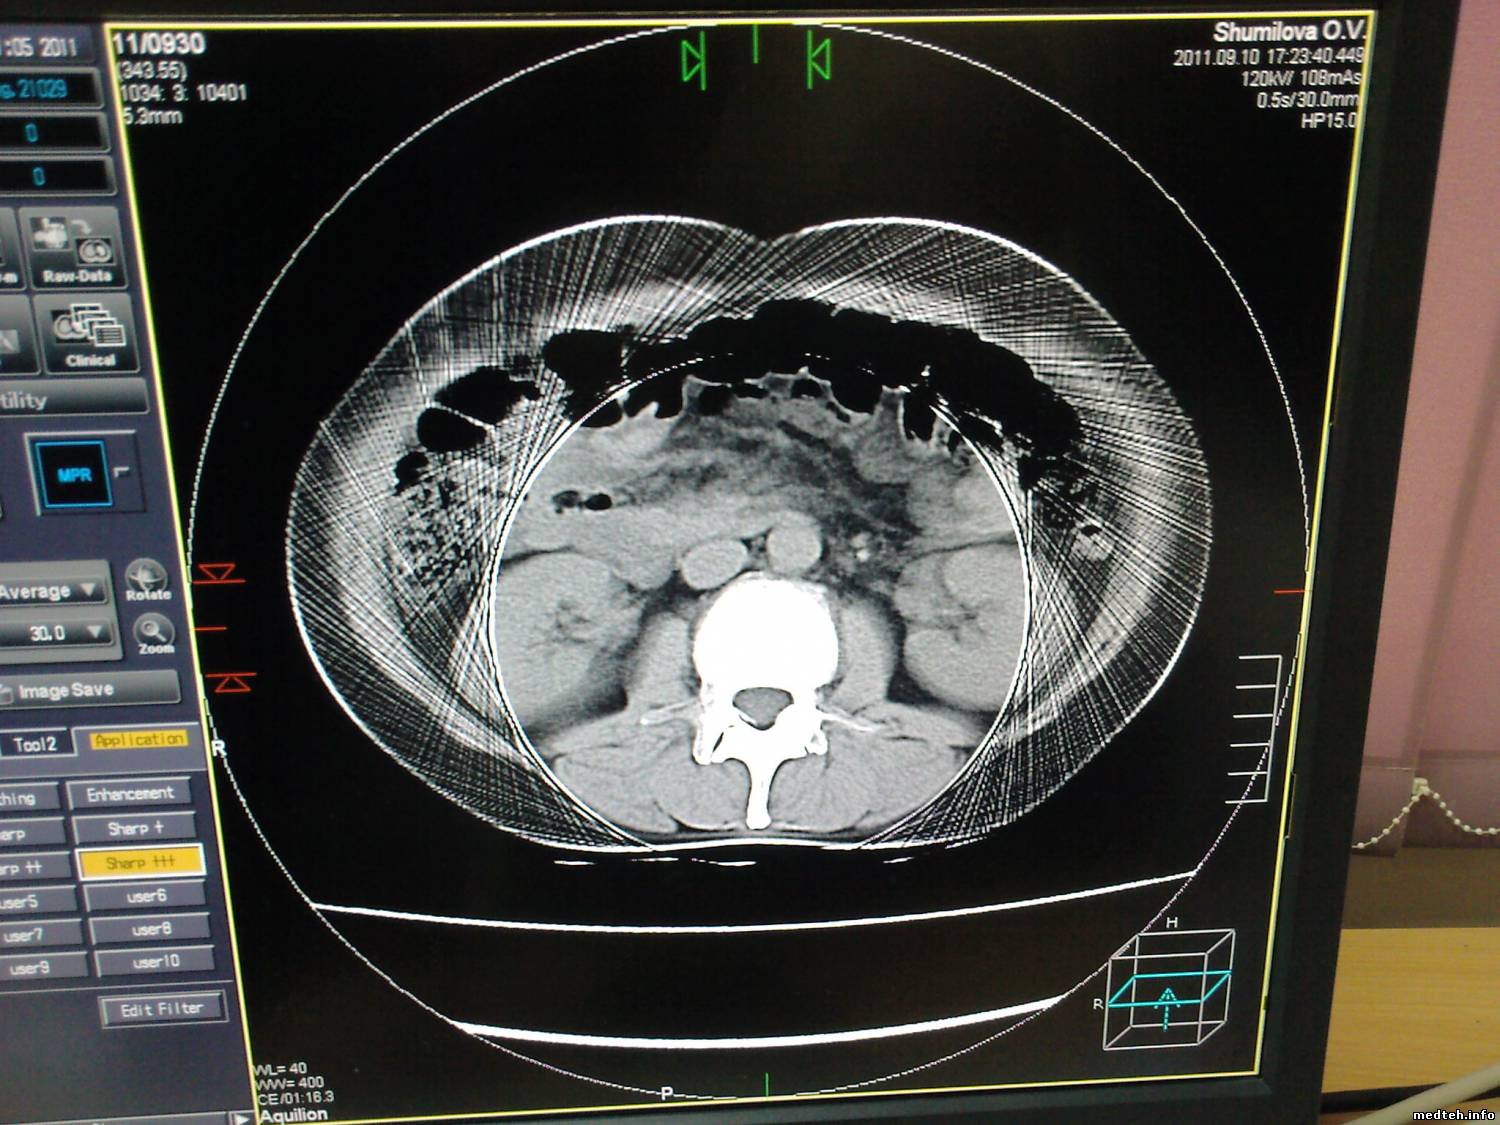

после подтопления кабинета, крыша протекла и по стенам пошли сырые разводы, на получаемых срезах появились "векторы направленности"

интересует момент - как объяснить грамотно проблему медперсоналу и что можно сделать на уровне пользователя?

4171846.jpg (133.2 Kb) · 4153610.jpg (204.8 Kb)